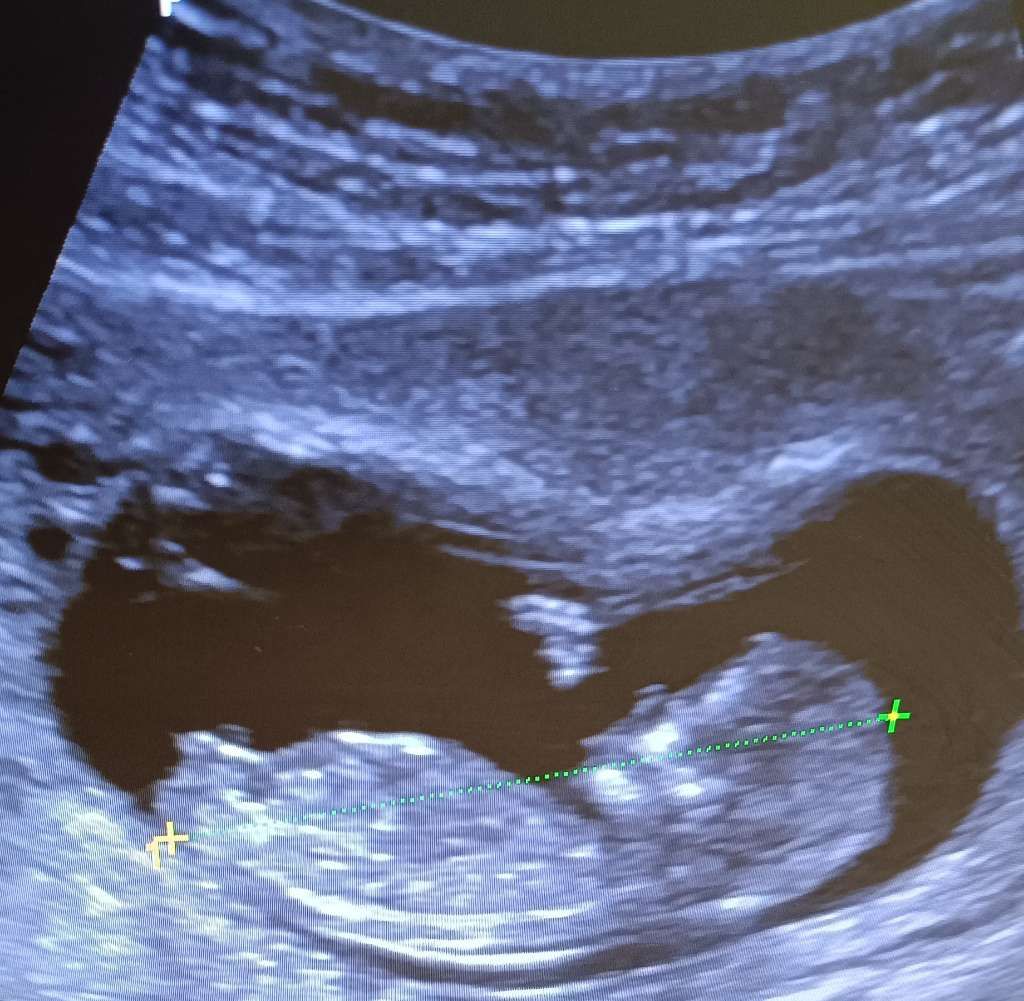

Chłopiec czy dziewczynka?

U mnie z takiego zdjęcia jest piękny chłopczyk. Myślę że u ciebie też będzie chlopiec. Pozdrawiam

Wyrostek na tym zdjęciu jest zupełnie inaczej ułożony niż na zdjęciu autorki :D Tutaj ewidentnie jest skierowany do góry jak u chłopczyka a u autorki na dwoje babka wróżyła moim zdaniem :D Możliwe, że u autorki za tydzień już będzie wyglądał jak u Ciebie, ale może też być dziewczynka moim zdaniem :D

U córki w 12+6 wyrostek był króciutki albo takie zdjęcie się akurat zrobiło 🤷🏼‍♀️ Syn z kolei miał taką jakby kuleczkę na końcu, więc też inaczej :D